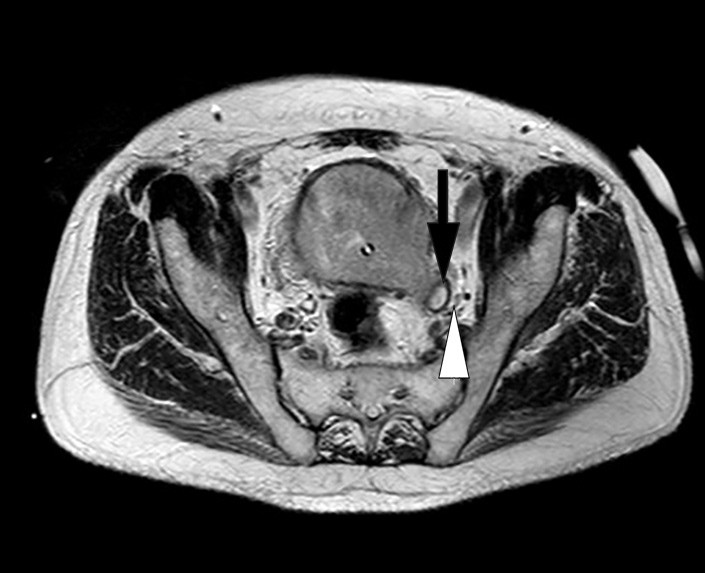

Like etter innleggelse ble det tatt CT urinveier uten intravenøs kontrast (fig 1). Denne viste bilateral uttalt hydronefrose og hydroureter med moderat atrofi av nyreparenkym. Det var forstørret urinblære med høyattenuerende innhold som ved blod. Cystoskopi ble gjort akutt og viste at blæren var fylt av koagler og papillomatøse tumorforandringer. Disse ble biopsert. Hematurikateter og bilaterale nefrostomikatetre ble anlagt. Biopsiene viste høygradig urotelialt karsinom, pT1GIII. Det ble ikke sett muskulatur. MR bekken viste uttalte tumorforandringer i nærmest hele blæren med innvekst i prostata og begge urinledere. Den viste også gjennombrudd av muscularis propria som ved minst T3-stadiet med muskelinvasiv blærecancer (fig 2, fig 3). For øvrig var det normale funn uten organmetastaser eller forstørrede lymfeknuter. Skjelettscintigrafi viste ikke tegn til metastaser. Ved nevropsykologisk testing fant man en sannsynlig mild kognitiv svik som ble planlagt fulgt opp etter utskrivning. Nyrefunksjonen bedret seg noe ved hjelp av avlastningen, og kreatininverdien stabiliserte seg rundt 190 μmol/l.